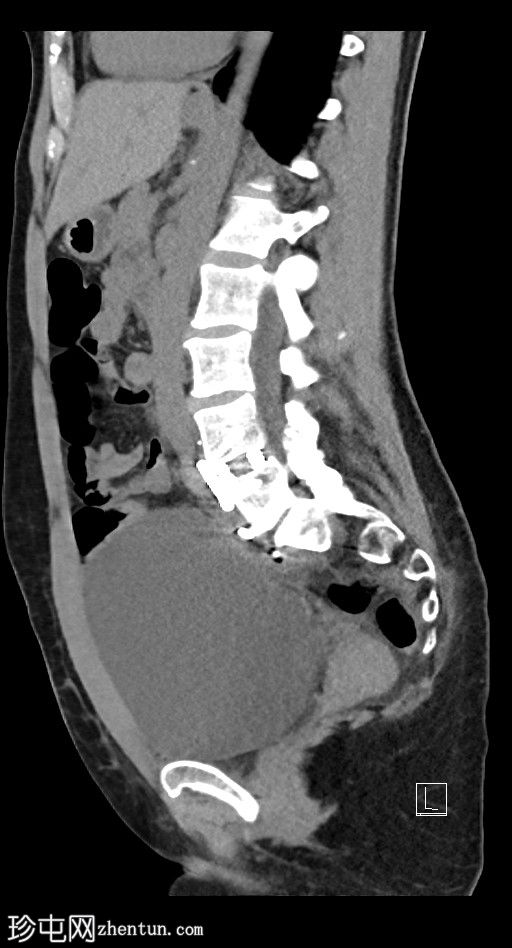

左侧腹膜后可见一巨大囊性肿块,位于左侧腰大肌内侧,紧邻多个手术夹(ALIF手术所用),这些手术夹紧贴囊性肿块后壁。

膀胱已行引流管减压,并被囊性肿块向右侧推移。

子宫和左侧附件在囊性肿块前方保持正常的脂肪间隙,因此附件囊性病变的可能性较小。

左侧输尿管难以辨认,因为它位于囊性肿块下缘后方。

左侧腹膜后巨大囊性病变,符合术后淋巴囊肿。鉴别诊断包括血清肿、尿瘤和脑脊液积聚,但脑脊液积聚的可能性较小。